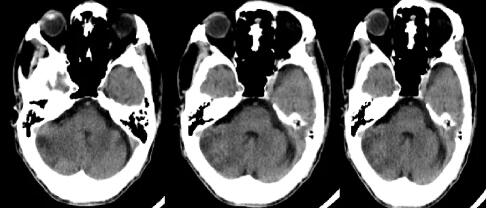

据林先生介绍,林大爷既往有高血压、房颤病史。自2011年以来,曾三次因脑梗住院,并遗留了饮水呛咳、肢体抖动等症状。入院后,我院副院长、神经内科专家王展航为患者完善了相关检查,发现他颅内有新的脑梗部位。为进一步明确病因,王展航又邀请了心理行为医学科专家及康复医学科专家进行会诊。经讨论分析,最终诊断患者为器质性精神障碍、右侧小脑出血性脑梗死(亚急性)及脑梗死后遗症。